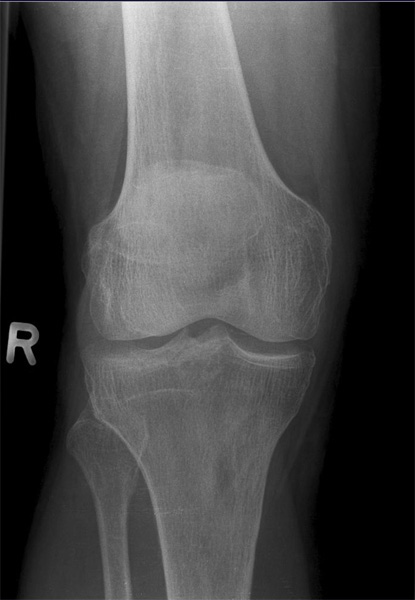

Kniegelenk

Knie a.p.

120_2.jpg

Fehler

Beide Gelenkfacetten des Tibiakopfes stellen sich oval dar, auf der einen Seite höher als auf der anderen; so kommt es im Röntgenbild zur Überschneidung mit den Gelenkkondylen des Femur und unter Umständen auch zu einer Verdeckung der Eminentia intercondylaris.

Abhilfe

Der Zentralstrahl muss bei jeder Knieaufnahme, sei es bei gestrecktem oder gebeugtem Knie, immer senkrecht auf die Längsachse der Tibia treffen.